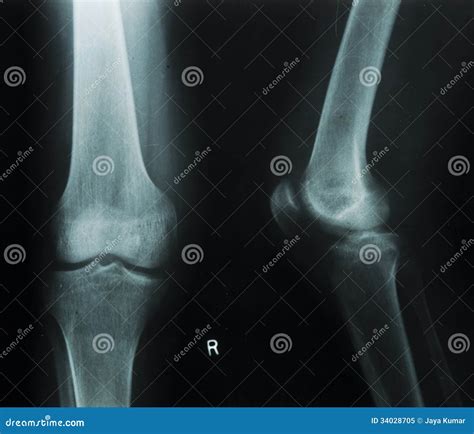

What Does a Normal Knee Xray Look Like?

A radiologist interprets a knee X-ray by looking at several key anatomical landmarks. When a report comes back as a normal knee xray, it means the technician and radiologist have observed the following components as being within standard clinical limits:

• Bone Integrity: There are no visible breaks, hairline fractures, or bony abnormalities.

• Joint Space: The gap between the femur (thigh bone) and the tibia (shin bone) is symmetrical and maintained, which suggests that the articular cartilage has not significantly eroded.

• Alignment: The bones are in their proper anatomical position, indicating there are no major dislocations or congenital malalignments.

• Soft Tissue Shadows: While X-rays are primarily for bones, they can sometimes show swelling or fluid accumulation (effusion) around the knee joint.

Because X-rays primarily capture dense tissue, a "normal" result confirms that the structural framework of your knee is intact. This is excellent news if you were concerned about a broken bone or severe bone deformity.